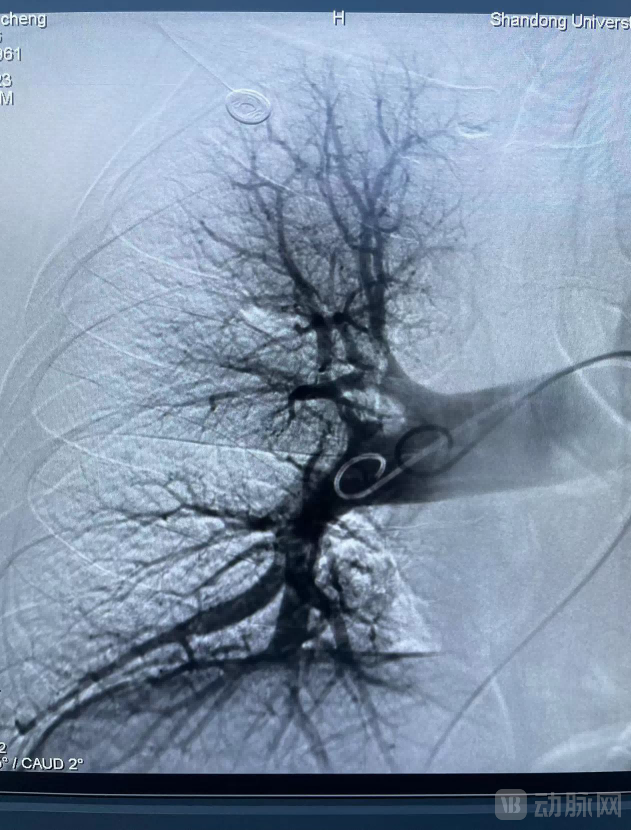

术中,医生将血栓抽吸导管沿导丝推送至右肺动脉干后进行抽吸,抽出大量条状及块状红色血栓。再将肺动脉血栓清除系统在残余栓块中释放网盘支架,吸附残余栓子后回收至抽吸导管,最后造影显示肺动脉血流通畅。

经血管造影确认血栓清除达到目标后结束手术。术后,患者测肺动脉压力明显下降。

术前造影